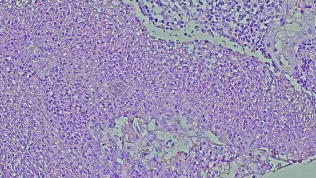

– Liczba kropli antybiotykowych bądź antybiotykosterydowych rocznie oscyluje u nas w granicach 5,5 mln przepisanych kropli. Oznacza to, że często w bardzo prozaicznych sytuacjach stosujemy antybiotyki, również w chorobach samoograniczających się, jak np. zapalenie spojówek – zauważa prof. Teper.

Dodaje, że w bardzo niewielu przypadkach ma to swoje uzasadnienie.